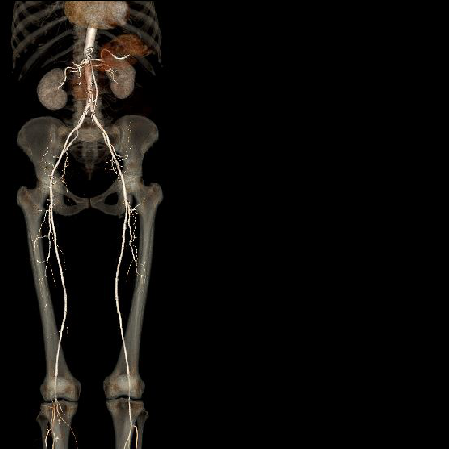

Peripheral angiography

Illustrations for clear understanding

Real scan images